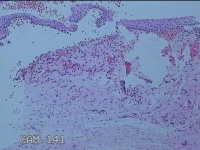

性别

女

年龄

42岁

临床诊断

围绝经期;宫颈上皮内瘤变?慢性宫颈炎

一般病史

宫颈7点醋白阳性

标本名称

宫颈7点组织

大体所见

灰白暗红色绿豆大组织一块。